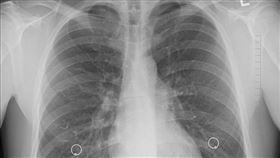

陽明山大縱走紀錄保持人 驚罹「肺腺癌」

肺癌連續13年高居國人癌症死因首位,以癌症死亡人數結...

肺癌女性9成不吸菸 小心家中2殺機

肺癌連續15年高居國人十大癌死因症之首,每年有近萬人...

小心感冒不單純 醫警告肺癌最會偽裝

台灣每年將近有九千人死於肺癌,死亡率所有癌症的第一名...

可怕!肺癌60%一發現就是晚期

台灣癌症基金會執行長賴基銘醫師。在三立新聞網「奕起聊...